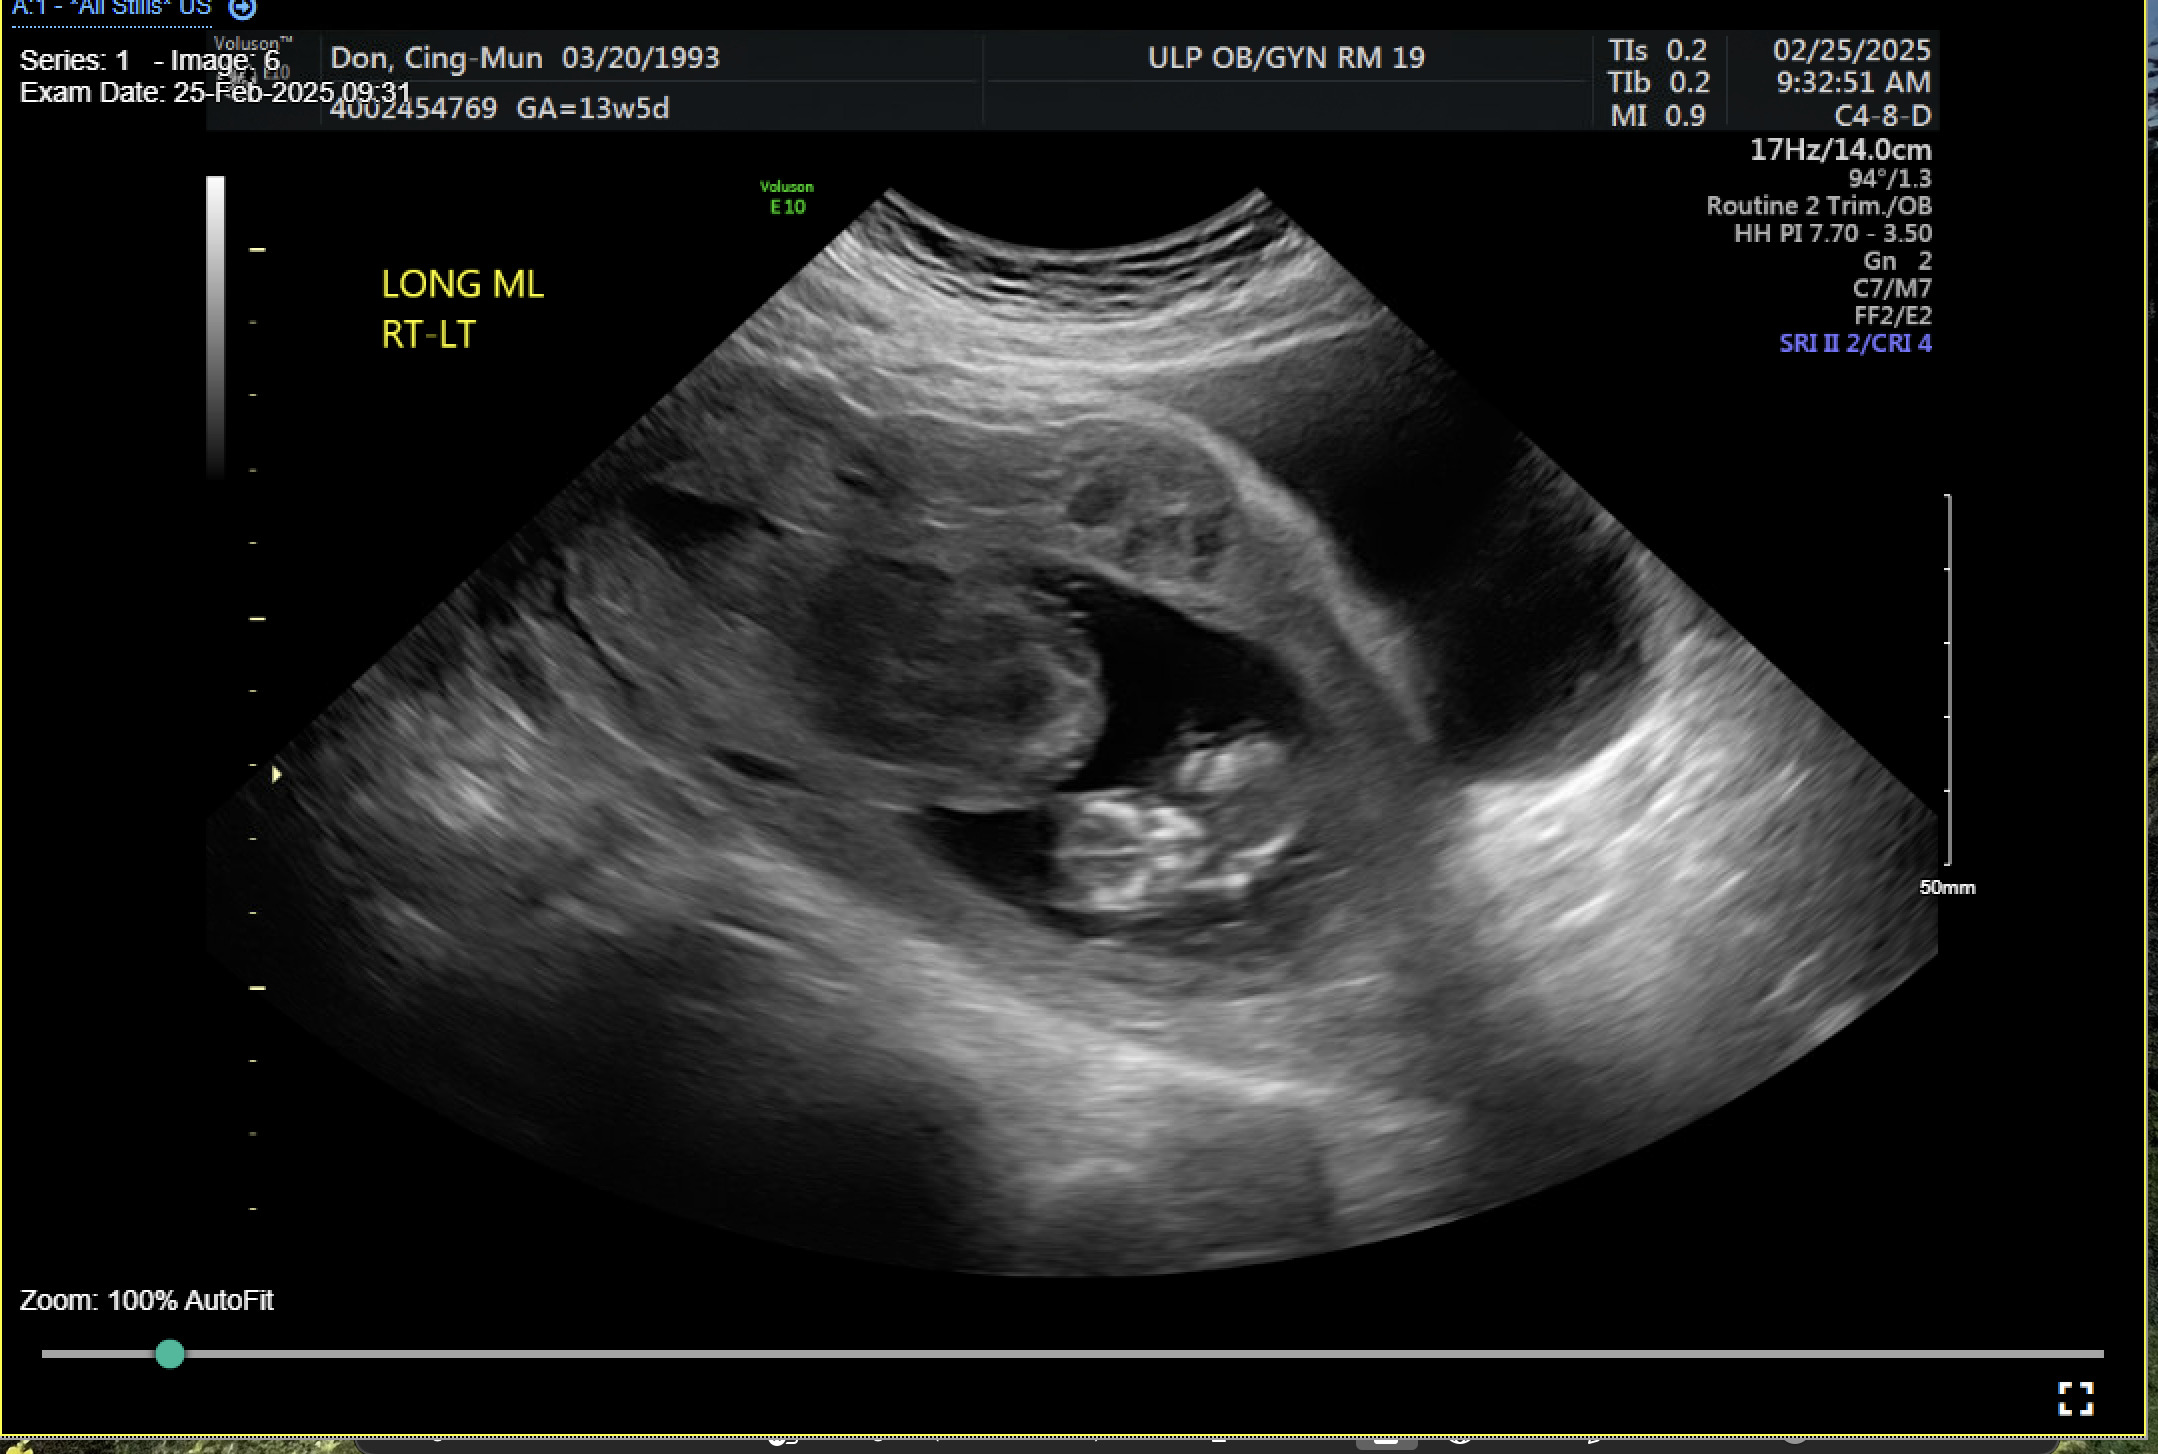

A 31-year-old gravida 2 para 1001 at 13 weeks and 6 days gestation by a 7-week ultrasound presented to ULH for surgical management of a missed abortion in the setting of suspected CSP versus PAS. The patient had previously been seen at an outside hospital emergency room for concerns of bleeding and pelvic pain. Ultrasound workups for these concerns were significant for viable intrauterine pregnancy and moderate subchorionic hemorrhage superiorly, grossly measuring 5 cm at the largest dimension. Two weeks after her initial emergency department (ED) visit, the patient was seen in our practice’s general obstetric clinic. A first trimester ultrasound was performed at this time and again demonstrated a 5 cm subchorionic hemorrhage (Figure 1). At this time, concern for CSP versus PAS was also noted, and the patient was advised to return for a follow-up scan. When the patient returned for further evaluation of placental pathology, ultrasound revealed fetal demise with absent fetal cardiac activity (Figure 2). Following discussion with the maternal fetal medicine (MFM) provider, the patient ultimately elected for surgical evacuation of the products of conception to mitigate spontaneous bleeding risks in the setting of CSP versus PAS.